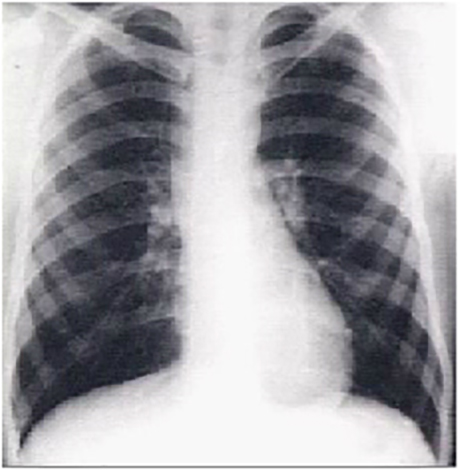

The PA view demonstrates dilatation of the ascending portion of the aorta as evidenced by a prominent bulge in the right mediastinal shadow. Note that the heart size is normal, as reflected by a cardiothoracic ratio less than 50%.